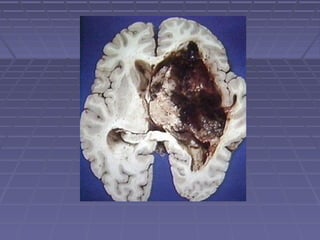

Alteraciones del aspectoAlteraciones del aspecto

 TURBIOTURBIO (predominio de PMN).(predominio de PMN). Se lo observaSe lo observa

en presencia de meningitis bacteriana.en presencia de meningitis bacteriana.

 ROJOROJO (hemorrágico) Puede ser de origen: -(hemorrágico) Puede ser de origen: -

TraumáticoTraumático: cuando la punción rompió un: cuando la punción rompió un

vaso sanguíneo en su paso al espaciovaso sanguíneo en su paso al espacio

subduralsubdural

 XANTOCROMICOXANTOCROMICO (amarillo) lo produce la(amarillo) lo produce la

oxihemoglobina de la sangre derramada enoxihemoglobina de la sangre derramada en

el espacio subaracnoideo y / o ventricular deel espacio subaracnoideo y / o ventricular de

varias horas. También se lo puede observarvarias horas. También se lo puede observar

en casos de ictericia y de aumento deen casos de ictericia y de aumento de

proteínas en el LCR independientemente deproteínas en el LCR independientemente de

su etiología.su etiología.